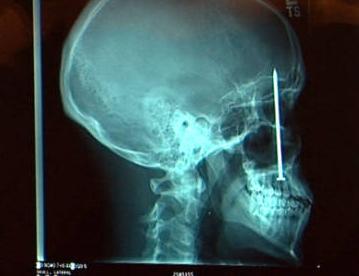

2. Bertindikan tombak nelayan

Emerson de Oliveira Abreu menemukan pengalaman yang sangat mengerikan saat menyelam di lepas pantai Rio de Janeiro ketika otaknya tertembus dengan tombak 6 inch. Laporan mengatakan, ia sendiri memiliki tombak yang menusuknya, menembak ke arah karang tetapi memantul kembali, dan akhirnya menyogok tulang tengkorak nya begitu dalam. Dia berada di bawah pisau (operasi) selama 5 jam sebelum ia sendiri terkejut dan menyatakan keluar dari bahaya. Wow!!!!!!!